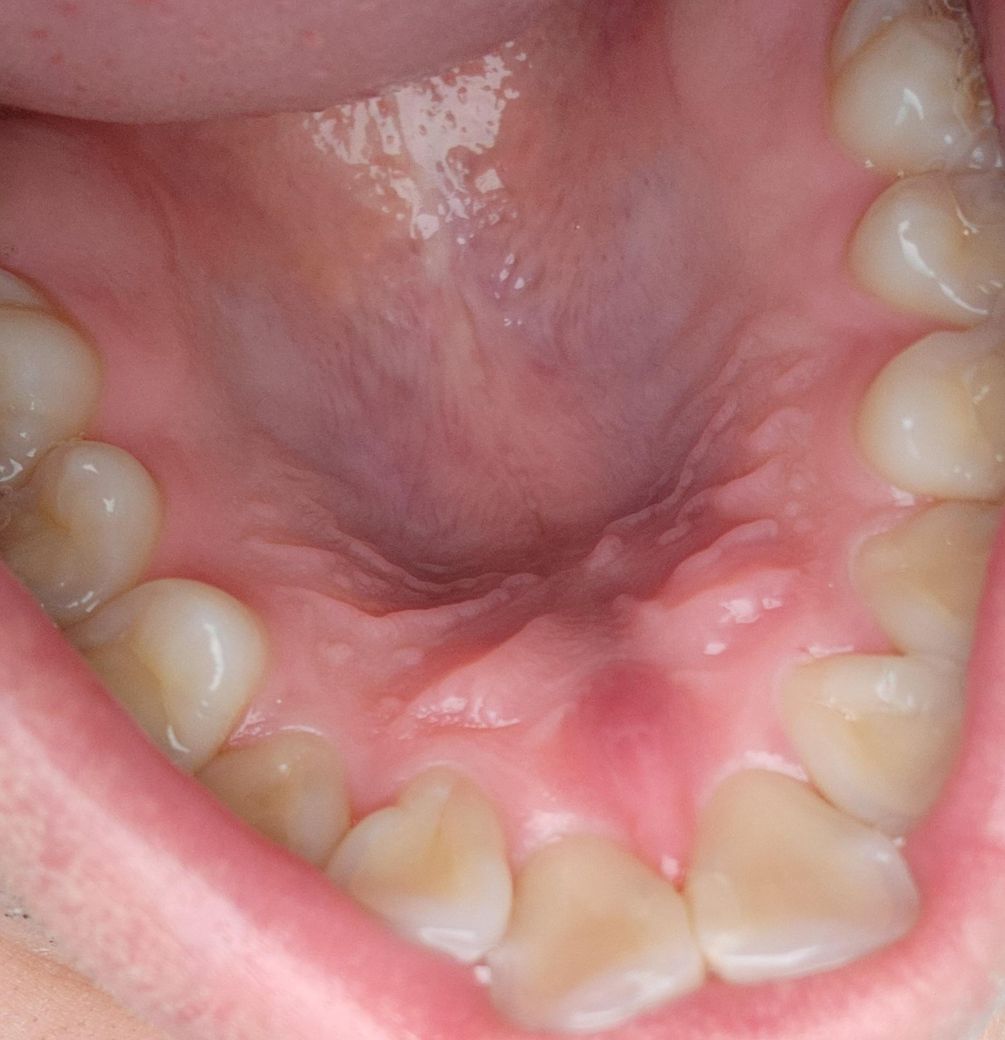

2주정도 돼니까 앞니전체가 시리고 가만있어도 욱씬거립니다. 거울로 여로모로 살펴 봤는데 충치도 없고 부은 것 같지도 않은데 잇몸 속에 문제가 생긴 걸까요?

• 1번 째 사진

사진으로 보아 정상적인 잇몸과 치아 상태로 보입니다. 계속 시리다면 일단 치과에 가서 스켈링 받기를 권합니다. 스켈링 받으면 시린 것 대부분 없어집니다.

사진에는 특별히 문제가 보이진 않지만 증상이 느껴진다면 치과에서 검사 받아보시는 게 좋겠습니다.